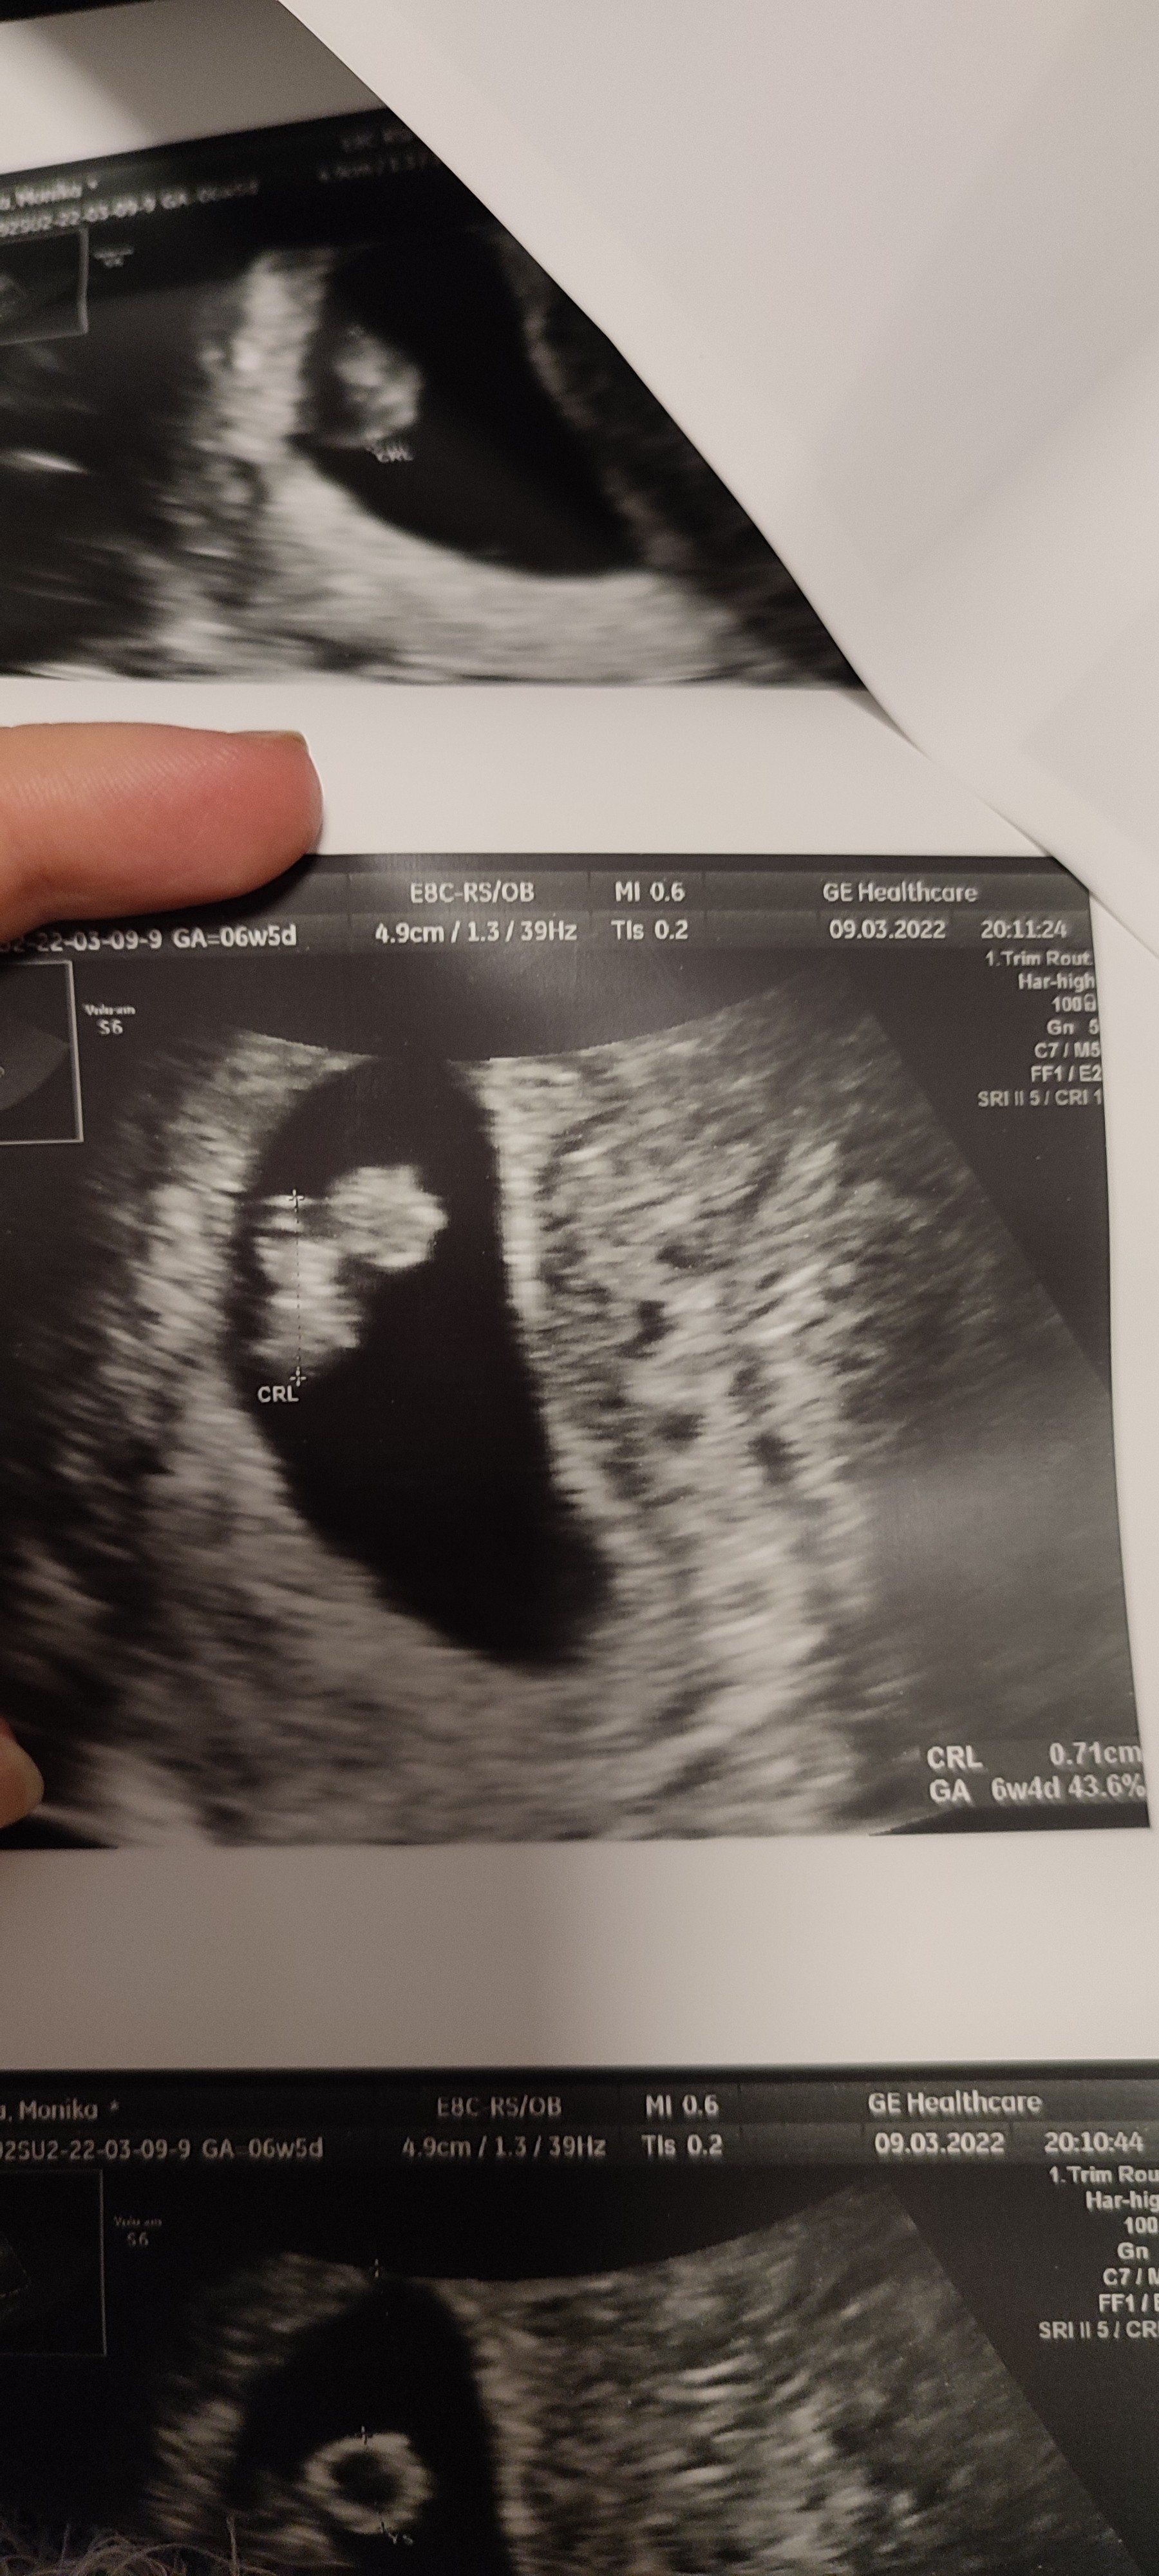

Oto moja fasolina 💕💕💕jednak niepotrzebnie się tak bałam, wszystko jest pięknie i co najważniejsze jest akcja serduszka 127 uderzeń na minutę. To bijące serduszko zrobiło na mnie ogromne wrażenie, jest to niesamowite:)

Załączniki

• IMG_20220309_203615.jpg

IMG_20220309_203615.jpg

1,1 MB · Wyświetleń: 110

• IMG_20220309_203527.jpg

IMG_20220309_203527.jpg

1,1 MB · Wyświetleń: 92